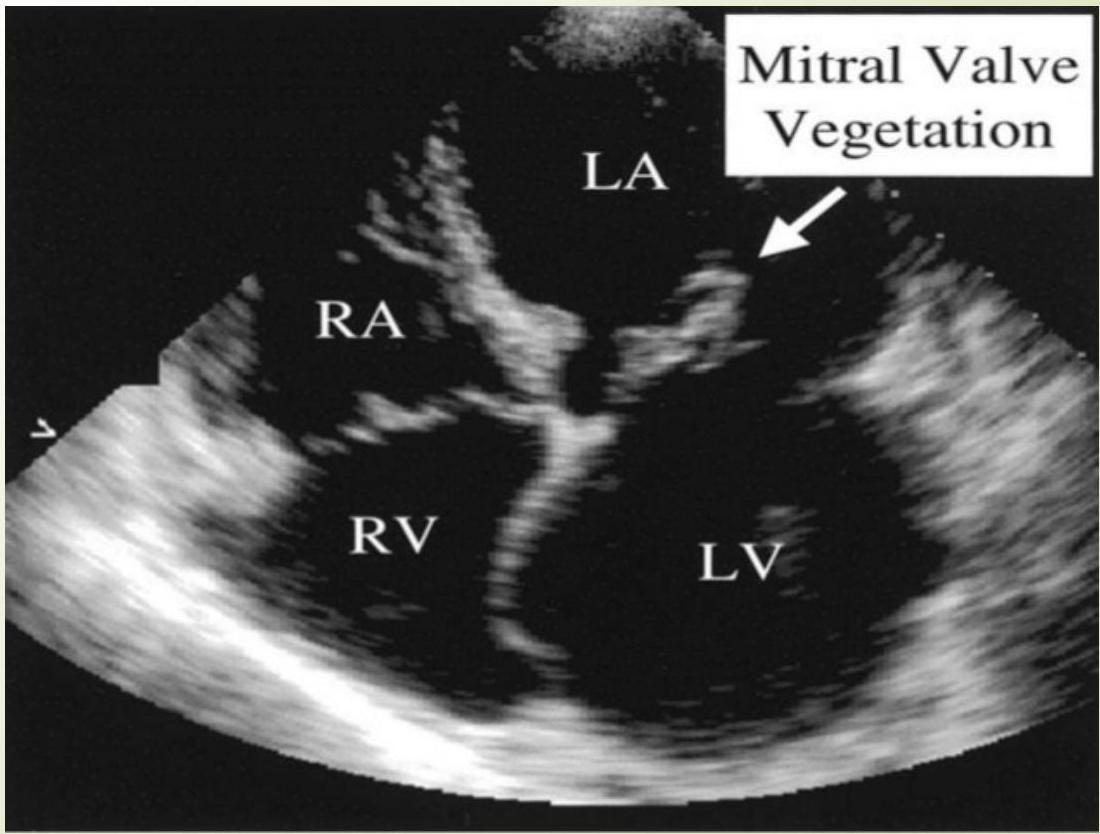

Echocardiography

- Indication: An echocardiogram for all patients with suspected IE.

- Findings: Vegetations, myocardial abscess, valve competence.

- TTE (Transthoracic): Less sensitive for vegetations than TEE; used for adolescents or overweight children.

- TEE (Transesophageal): More sensitive.

Echocardiography Images

Mitral Valve Vegetation